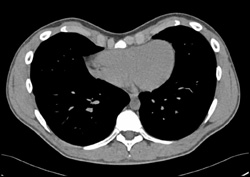

Breast Cancer With Axillary Nodes